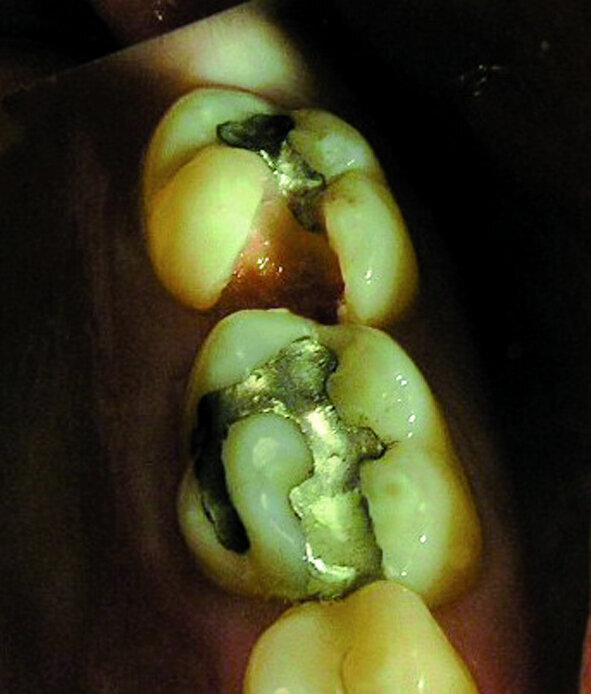

Les deuxièmes prémolaires peuvent être résumées par les mots « je veux créer » ou « mon moi créatif » (Fig. 3). La deuxième prémolaire supérieure droite symbolise ce que l’on veut développer dans le monde extérieur, nos enfants ou nos hobbies, et la deuxième prémolaire supérieure gauche nos dons naturels. La deuxième prémolaire inférieure droite, similairement à la première prémolaire adjacente, témoigne de notre capacité d’accomplir nos projets, particulièrement dans le domaine du travail. Ainsi, après la restauration d’une anodontie au moyen d’un bridge sur inlay, une jeune patiente dans l’indécision a terminé brillamment ses études au grand bonheur de ses parents (Fig. 4). Par contre les figures 5 et 6 sont des photographies de patients chez qui l’évolution professionnelle se place toujours au second rang des priorités.